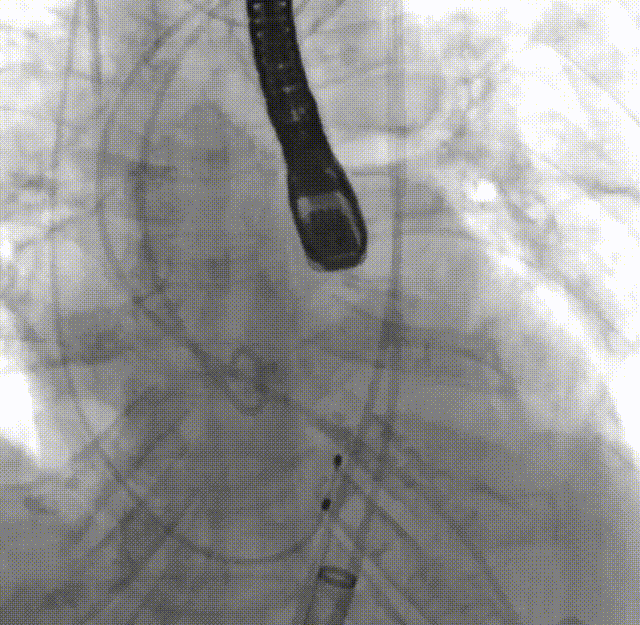

手术过程概览

主动脉根部造影,反流明显

瓣上3mm定位

释放到工作位下滑至零位

瓣架打平,同轴性好

超声看左冠窦侧6mm左右

完全释放,无反流

超声看完全释放下滑至7mm

几乎无反流

几乎无瓣周漏

观察后无下滑